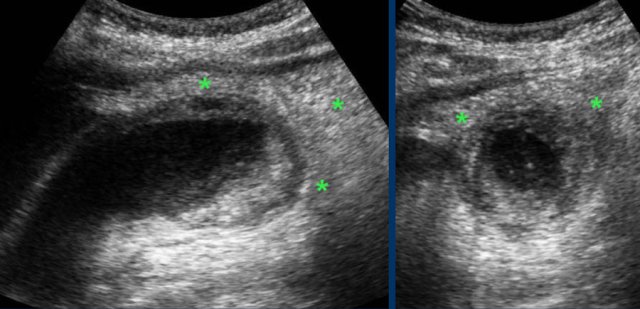

Advanced cholecystitis with inflamed fat ( asterisks) around the gallbladder fundus.

This represents the omentum, migrating towards the gallbladder in order to wall-off a possible perforation.

The images show a longstanding acute cholecystitis.

Note the large area of inflamed and indurated fat (asterisks) and the relatively small, somewhat compressible gallbladder.

This reflects a lumen filled with pus where the diseased mucosa is not capable of producing mucus under pressure anymore.

Drainage revealed pus.